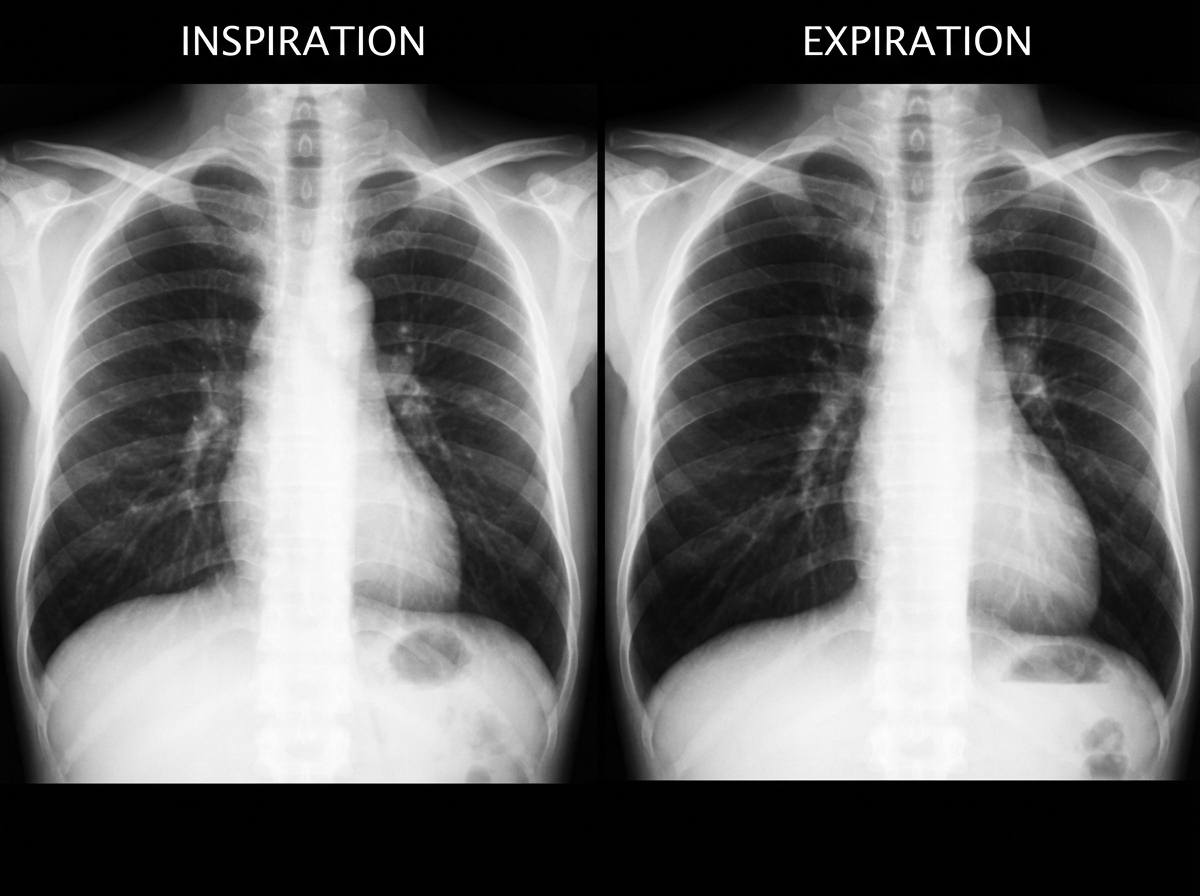

A previously healthy 2-year-old black child has developed a chronic cough during the previous 6 weeks. He has been seen in different emergency rooms on two occasions during this period and has been placed on antibiotics for pneumonia. Upon auscultation, you hear normal breath sounds on the left. On the right side, you hear decreased air movement during inspiration but no air movement upon expiration. Inspiratory and expiratory radiographs of the chest are shown. Which of the following is the most appropriate next step in making the diagnosis in this patient?

Explanation: ***Consult pediatric surgery for bronchoscopy*** - The **asymmetric breath sounds** with decreased air movement on inspiration and **no air movement on expiration** suggests a **check-valve mechanism** consistent with **foreign body aspiration**. - **Air trapping** visible on expiratory chest radiographs in a **2-year-old toddler** with recurrent unilateral pneumonia strongly indicates **bronchoscopy** is needed for both diagnosis and removal. *Measure the patient's sweat chloride* - **Sweat chloride testing** is used to diagnose **cystic fibrosis**, which typically presents with **bilateral lung involvement** and **failure to thrive**. - The **unilateral findings** and **check-valve mechanism** are not characteristic of cystic fibrosis. *Prescribe broad-spectrum oral antibiotics* - **Antibiotics** have already been tried twice without resolution, indicating this is not a **bacterial pneumonia**. - The **mechanical obstruction** from a foreign body requires **physical removal**, not antimicrobial therapy. *Initiate a trial of inhaled β-agonists* - **β-agonists** are used for **bronchospasm** in conditions like asthma, which typically causes **bilateral wheezing**. - The **unilateral air trapping** and **check-valve pattern** indicate **mechanical obstruction**, not bronchospasm.